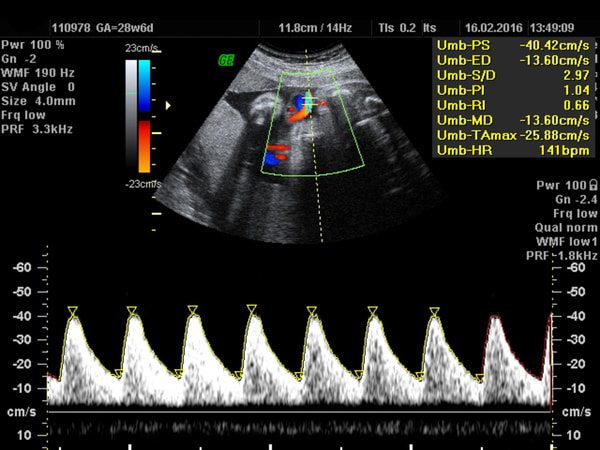

If you find your unborn baby has reduced movement, particularly in the 3rd trimester, Numi Scan can complete a well-being scan that focuses on the development of your unborn baby. During this examination we can assess the umbilical artery blood flow to ensure the artery is supplying the right amount of blood, check growth measurements, check for fetal movement, amniotic fluid levels & establish placenta position. For more information & to make a booking visit www.numiscan.co.uk